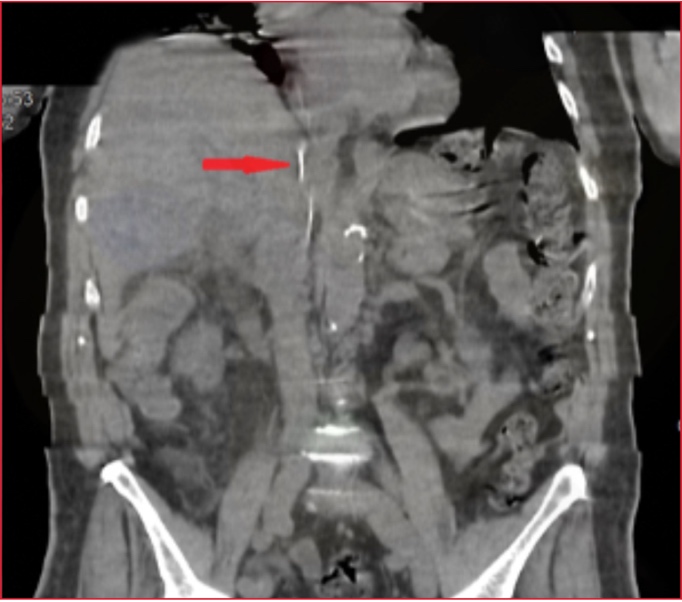

Se completó el

estudio con una tomografía computarizada, que mostró la progresión de la guía

hasta la vena cava inferior tanto en el corte coronal (Figura 2) como en el

corte axial (Figura 3).

Figura 2. Tomografía computarizada (corte coronal). Se observa la guía metálica progresando a través de la vena cava inferior (flecha roja).